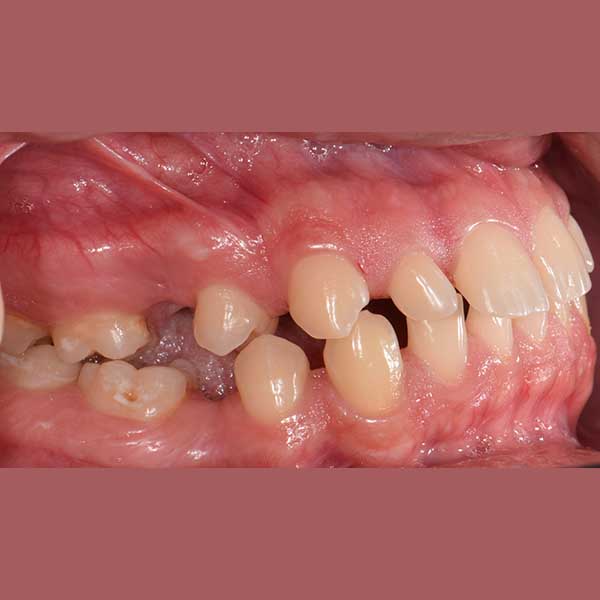

AFTER

Our friend’s case was treated with fixed braces, closing the frontal spaces and returning them to their original position. In the second stage, it was agreed to implant the missing back teeth.